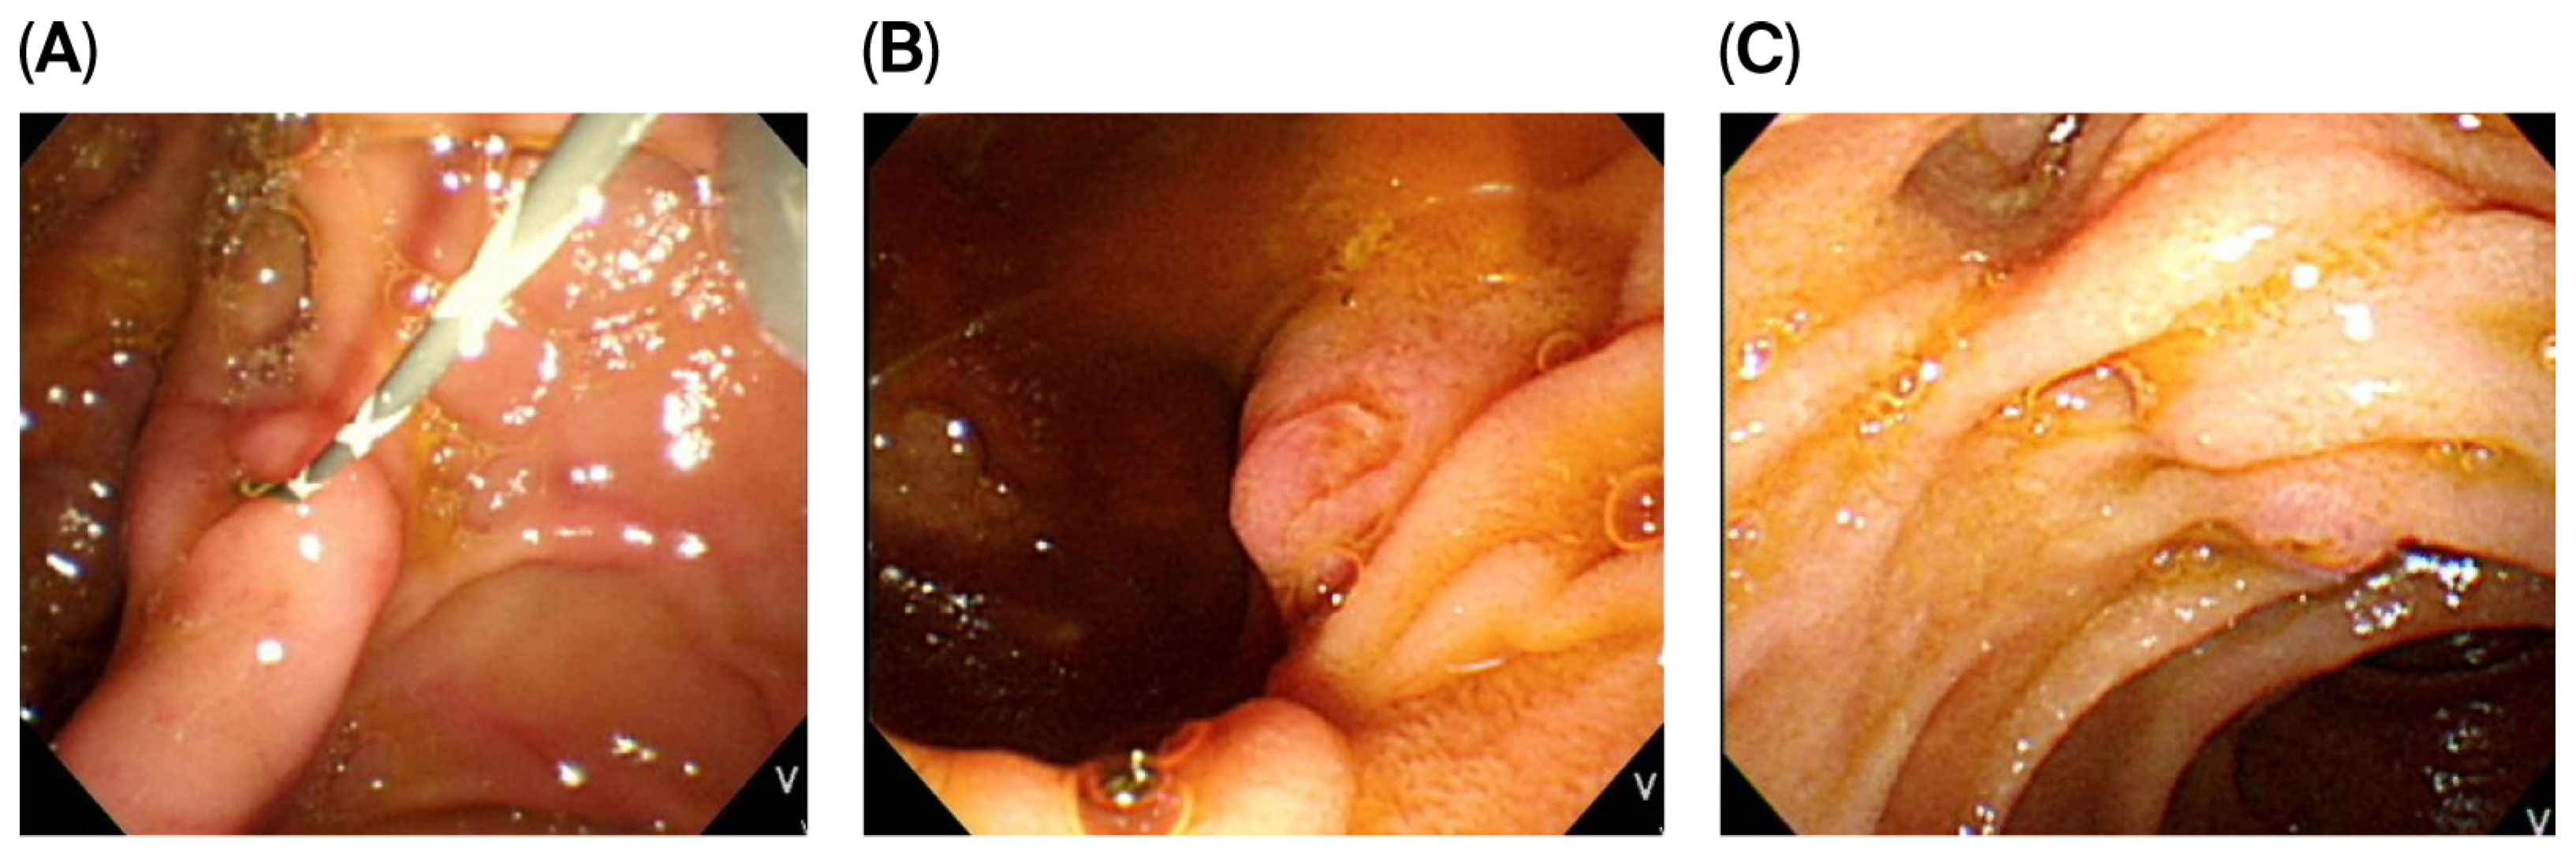

2.3. Morphology of the Major Duodenum Papilla